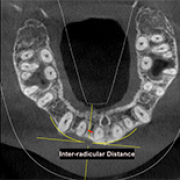

Evaluation of Orthodontic Mini-Implant Placement in the Maxillary Anterior Alveolar Region in 15 Patients by Cone Beam Computed Tomography at a Single Center in South India

Arathi Murugesan, S.P. Saravana Dinesh, Srirengalakshmi Muthuswamy Pandian, Lichi Ashwin Solanki, Abdulrahman Alshehri, Wael Awadh, Khalid J. Alzahrani

, Khalaf F. Alsharif, Mrim M. Alnfiai, Reji Mathew, Tarek El-Bialy

, Hosam Ali Baeshen, Shilpa Bhandi, A. Thirumal Raj, Shankargouda Patil